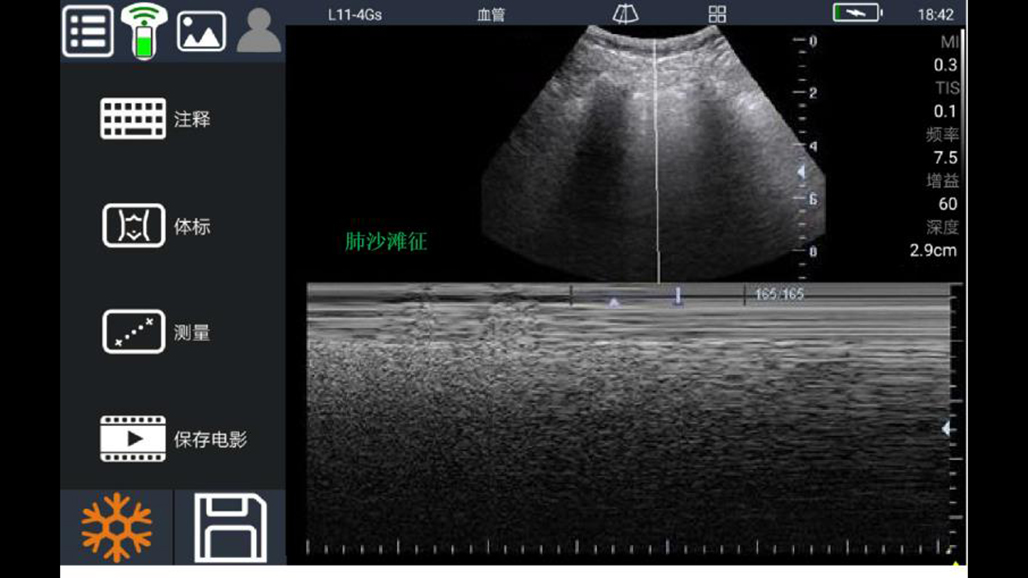

• 大凸

腹部

肾脏

妇科产科

心脏

肺等